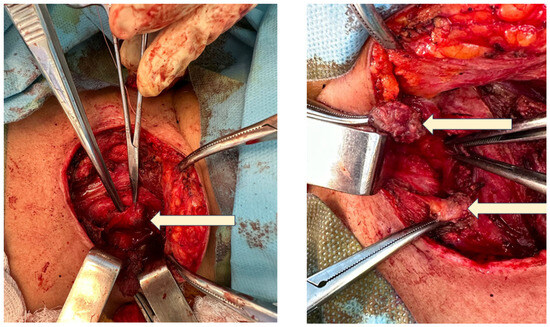

4.1.2. Initial Thyroidectomy and Removal of the Ectopic Thyroid Tissue

4.1.4. Redo Thyroidectomy